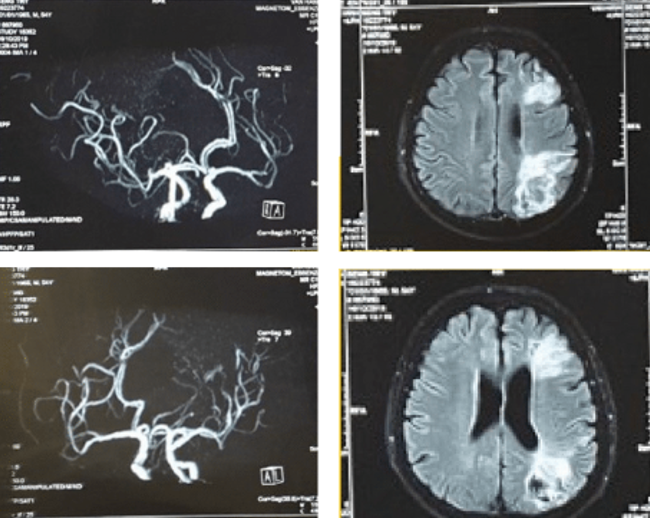

Đau đầu cấp tính do tắc mạch máu não ở bệnh nhân nam 49 tuổi, có tiền căn Tăng huyết áp

Đau đầu ở một bệnh nhân nam bị dị dạng mạch máu não